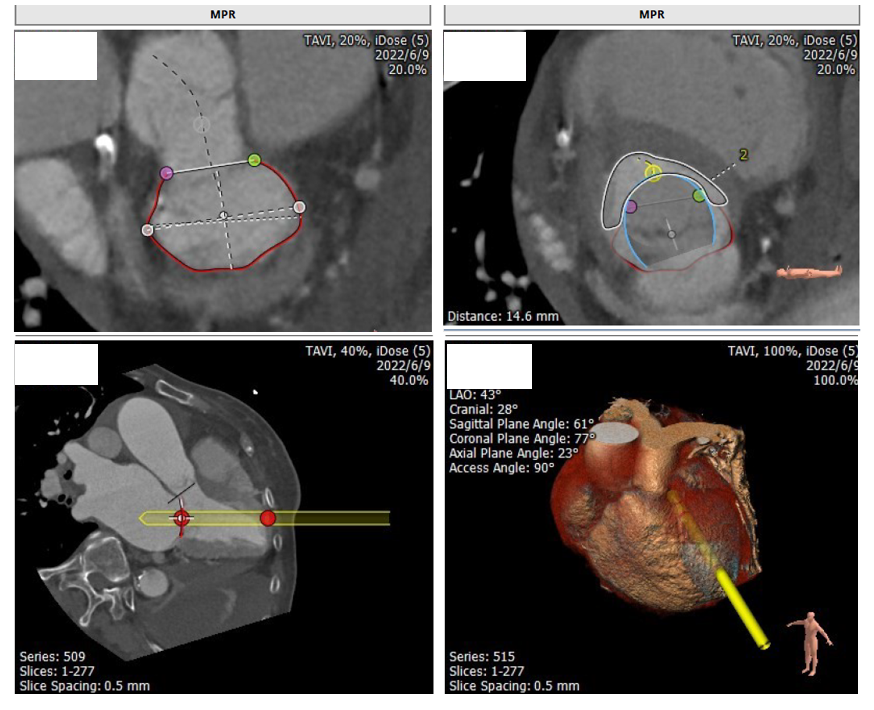

经过浙一心外科MDT团队综合讨,论评估患者病情后,由于缺血性心肌病、心功能储备极差、外科手术风险高。决定进行极其微创的经导管二尖瓣置换,采用以心医疗自主研发的MitraFix®经导管二尖瓣植入器械。术前CTA测算瓣环AP径29.6mm 、CC径37.2mm、 周长获得直径34.8mm 、使用MitraFix®29#瓣膜 Neo LVOT面积可。各项参数完全符合核心实验室入选标准。

经过浙一心外科MDT团队综合讨,论评估患者病情后,由于缺血性心肌病、心功能储备极差、外科手术风险高。决定进行极其微创的经导管二尖瓣置换,采用以心医疗自主研发的MitraFix®经导管二尖瓣植入器械。术前CTA测算瓣环AP径35.9 mm 、CC径36.6 mm、 周长获得直径37.9mm、使用MitraFix®34#瓣膜 Neo LVOT面积可。各项参数完全符合核心实验室入选标准。